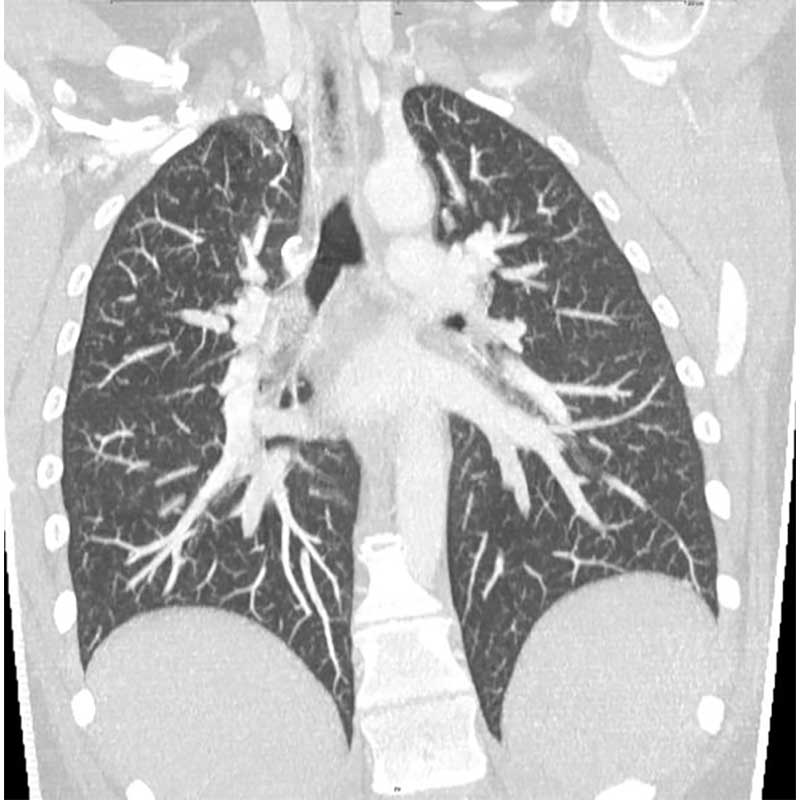

Hochspezialisierte Modalitäten (Volldigitales Röntgen, 80-Zeilen Multidetektor Spiral-CT, 3-Tesla MRT) wenden in ihrer Rekonstruktions-Software sowie nachgeschalteten diagnostische Algorithmen künstlicher Intelligenz an und gewährleisten eine hoch akkurate Diagnostik bei schonender Patientenversorgung. Neben Methoden zur automatischen Detektion und Volumetrie pathologischer Areale kommen Untersuchungsverfahren zur Lungenperfusion und -ventilation zum Einsatz. Die CT-gesteuerte Bronchusnavigation wird neben anderen Methoden als minimal-invasives Biopsieverfahren eingesetzt. Bei diesem Bildfusionsverfahren fungieren hoch aufgelöste CT-Datensätze als interaktive Karte (Roadmap) zur bronchoskopischen Biopsiegewinnung und ergänzen neben der CT-gesteuerten transthorakalen Biopsie die Kryobiopsie und offene Lungenbiopsie-Verfahren.

Die Sarkoidose ist die häufigste Erkrankung des Lungengerüstes überhaupt. Patientinnen und Patienten suchen regelmäßig mit pulmonalen Symptomen wie Luftnot oder Husten die Lungenfachärztin bzw. den Lungenfacharzt auf. Fast bei der Hälfte aller Fälle werden die Granulome jedoch als Zufallsbefund bei symptomfreien Patientinnen und Patienten entdeckt. Das Röntgenbild der Lunge löst dann weitere Tests aus bzw. die computertomographische Bildgebung. Die Erkrankung lässt sich nicht regelhaft an einem Röntgenbild allein diagnostizieren.

Es gibt vielfältige morphologische Erscheinungsbilder der Erkrankung in der Lunge mit Überlappungen zu anderen Erkrankungen. Die Diagnose in der Computertomographie kann deshalb anspruchsvoll sein. Dabei ist unklar, warum sich die Sarkoidose im Einzelfall so unterschiedlich verhält – abgesehen von der Frage der Organbeteiligung. Die Verlaufsformen werden in akut oder chronisch eingeteilt. Akute Formen der Sarkoidose beginnen häufig mit Gewichtsverlust, Abgeschlagenheit, Nachtschweiß oder Temperaturen 37,5°C bis 37,9°C (subfebril). Die Kombination von Gelenkschmerzen, bläulichem Hautausschlag und Fieber ist als sogenanntes Löfgren-Syndrom bekannt. Entzündungsparameter im Blutserum schließen eine erhöhte Konzentration von Interleukin-2-Rezeptoren ein. Die akute Sarkoidose betrifft neben der Lunge oft weitere Organe, z.B. lymphatische Organe, Milz, Leber und Knochenmark. Akute Verlaufsformen ohne Beteiligung der Milz tendieren zur Spontanheilung (Spontanremission). Wiederauftreten (Rezidive) manifestiert sich hingegen meistens mit akuten Symptomen.